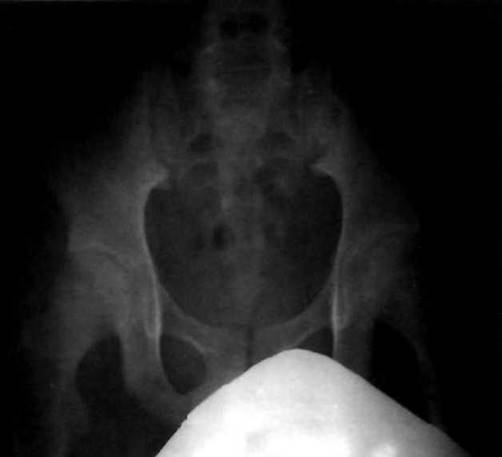

Рис. 23-19. Рентгенограмма таза больного ЮАС: двусторонний сакро- илеит її стадии с симптомом «псевдорасширения» суставной щели.